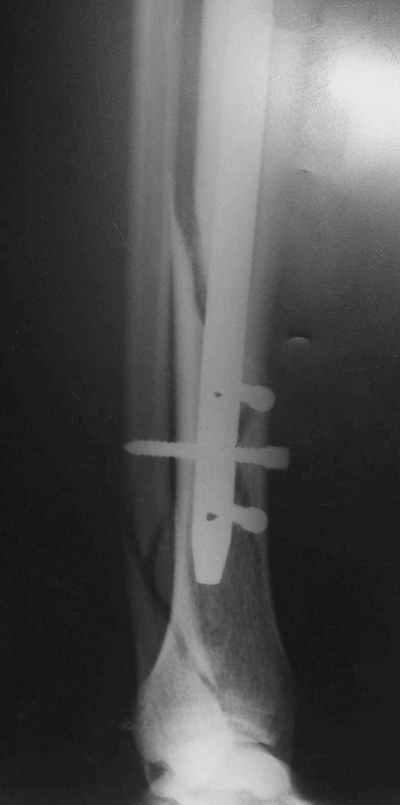

Не удается отправить первичные снимки. А что скажите по имеющимся?!

Выполненный остосинтез нестабилен. Штифт надо заменить по "размеру" на солидный, дистльно три запирающих винта. Успехов!

Перелом спиральный, то есть низкоэнергетический, так что со сращением дело обстоит уже неплохо, лишь бы "костоеда" не развилась. Отломки выглядят уже стабилизированными костной мозолью, так что довводить винты, наверно, уже незачем. Разве что при клинической оценке подвижность еще есть - тогда можно для стабилизации наложить простейший аппарат, не опасаясь контакта его элементов с гвоздем, поскольку места в дистальном метафизе оставлено более чем достаточно.

С Александром согласен, нет необходимости делать дополнительные усилия для сращения, не большая компрессия аппаратом из двух колец и полная нагрузка доделает работу.

Уже имеется какое-то сращение. А в этих условиях выполнить реостеосинтез гвоздём не дольше, чем "накинуть" аппарат из двух колец. Ходить можно сразу с полной нагрузкой, да и качество жизни пациента без аппарата лучше.